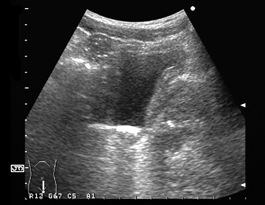

突然排尿障害が発症した症例で、前立腺部尿道に1cm大の結石の嵌頓を認めた。膀胱壁は平滑である。腎結石が落下したものと考えられる。落下結石の大半は自然排石される。 |